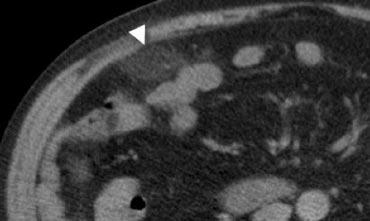

Hình 4. Nam giới 43 tuổi bị viêm ruột thừa. CT có tiêm thuốc cản quang cho thấy ruột thừa giãn chứa dịch (mũi tên) với thâm nhiễm mỡ quanh ruột thừa.

Trên CT, ruột thừa viêm được bao quanh bởi dấu hiệu thâm nhiễm mỡ (Hình 4).